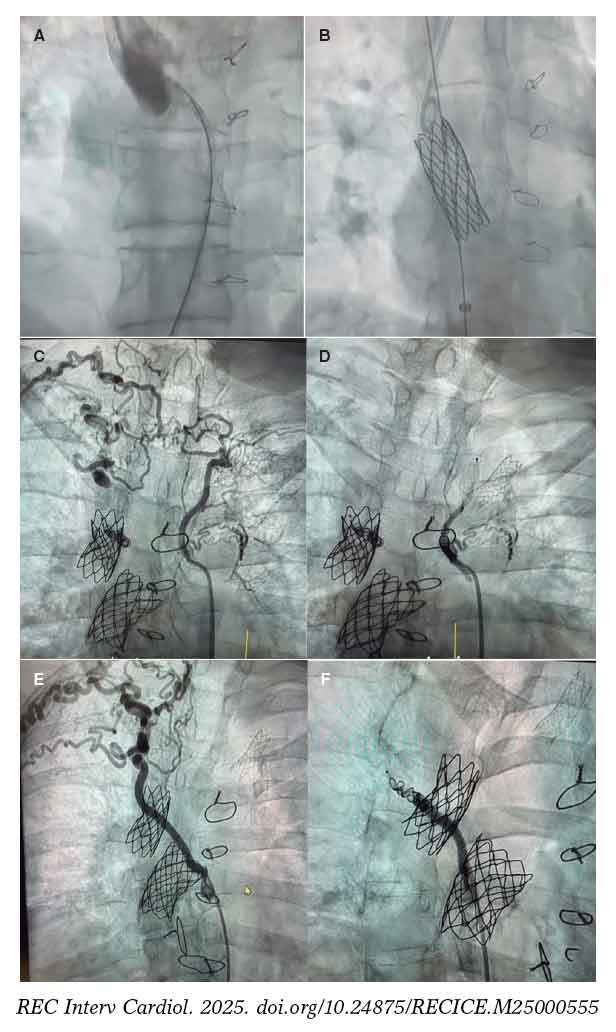

In our setting, the joint work model established since 2015 between pediatric and adult teams illustrates this philosophy. It is not just about sharing a cath lab but generating shared spaces for discussion and decision-making through multidisciplinary clinical sessions to standardize criteria and enable individualized strategy planning. A recent example reflecting the benefits of this collaborative model is a Fontan optimization case involving stenting and collateral closure. The patient was a 41-year-old woman with complex congenital heart disease and single-ventricle physiology—characterized by atrioventricular concordance with ventriculoarterial discordance, complete transposition of the great arteries, a large ventricular septal defect, pulmonary stenosis, and right ventricular hypoplasia—who had undergone multiple surgical procedures (Blalock–Taussig shunt at 13 months, systemic–pulmonary shunt at 2.5 years, bidirectional Glenn at 9 years, and extracardiac Fontan at 17 years). She exhibited reduced functional capacity and Fontan-associated hepatopathy. Cardiac catheterization confirmed a severely calcified Fontan conduit with significant stenosis at its insertion into the right pulmonary artery. Balloon sizing was performed, followed by implantation of a covered stent postdilated with a 20-mm balloon, achieving a good result. A marked stenosis at the Glenn-to–right pulmonary artery anastomosis was confirmed via right internal jugular vein, and a 34 mm bare-metal stent was implanted (figure 1A,B). The aortography performed via arterial access revealed the presence of large aortopulmonary collaterals supplying the 2 upper lung lobes, which were successfully occluded. The first one, toward the right and left upper lobes, was closed using an Amplatzer Vascular Plug 4 (Abbott Cardiovascular, United States) and coils; the second, toward the right upper lobe, was also closed with an Amplatzer Vascular Plug 4 and coils (figure 1C,F). This case illustrates the synergy between pediatric and adult interventional cardiologists in completing treatment.

Figure 1. Fontan optimization. A: stenosis at the Glenn–right pulmonary artery anastomosis. B: bare-metal stent implanted in the stenosis. C: large aortopulmonary collateral supplying the right and left upper lung lobes. D: occlusion of this collateral. E: large aortopulmonary collateral supplying the right upper lobe. F: occlusion of the collateral.